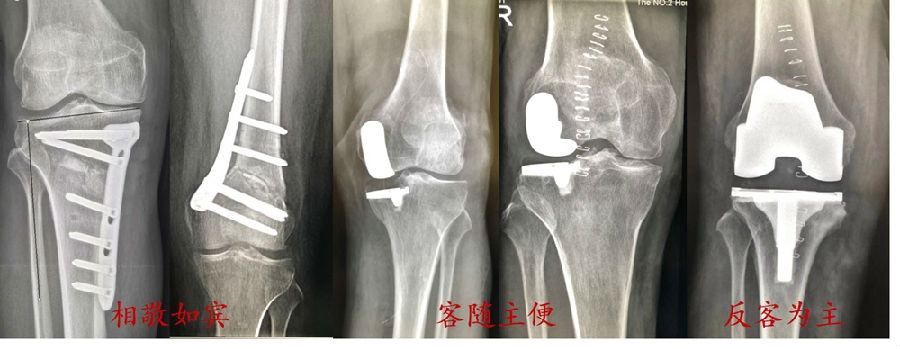

OA的外科阶梯治疗方式

回顾膝关节OA的外科阶梯治疗方式,包括截骨术(HTO/DFO),单髁置换(内侧、外侧),全膝置换术。

截骨后不同关节线倾斜方向的影响:

内倾-关节线由外上至内下倾斜-剪切力较大;外倾-关节线由内上至外下倾斜-剪切力较小。

如果单纯从胫骨侧或股骨侧矫正下肢内翻畸形:

矫正度数大;截骨后关节线出现由外上至内下倾斜>4°,软骨承受剪切应力,关节囊韧带承受异常应力,将导致持续的症状。